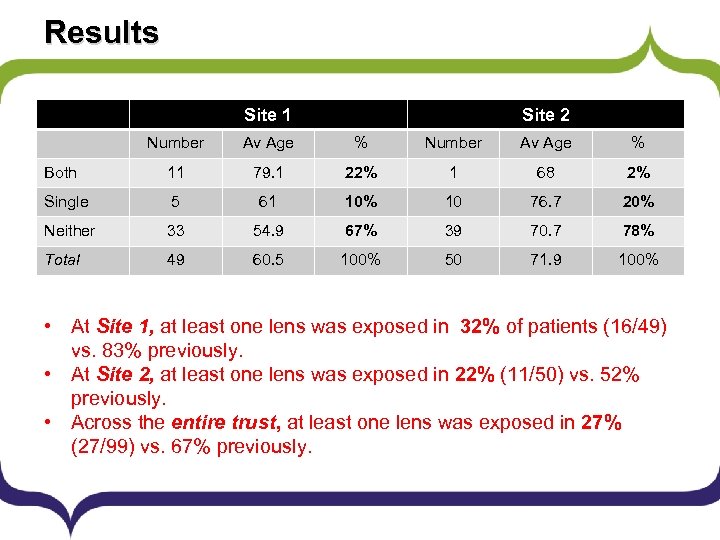

Results Site 1 Site 2 Number Av Age % Both 11 79. 1 22% 1 68 2% Single 5 61 10% 10 76. 7 20% Neither 33 54. 9 67% 39 70. 7 78% Total 49 60. 5 100% 50 71. 9 100% • At Site 1, at least one lens was exposed in 32% of patients (16/49) vs. 83% previously. • At Site 2, at least one lens was exposed in 22% (11/50) vs. 52% previously. • Across the entire trust, at least one lens was exposed in 27% (27/99) vs. 67% previously.